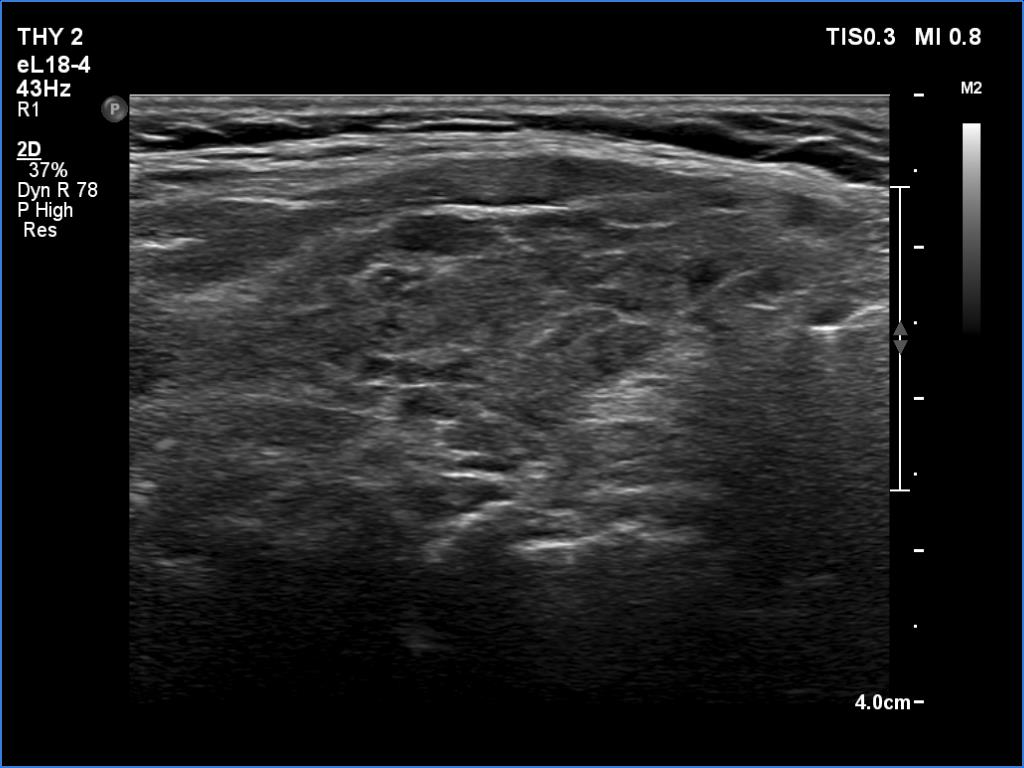

Ultrasonography. The thyroid was minimally hypoechoic and had several discrete areas of various echogenicities. None of these lesions corresponded to true nodule.